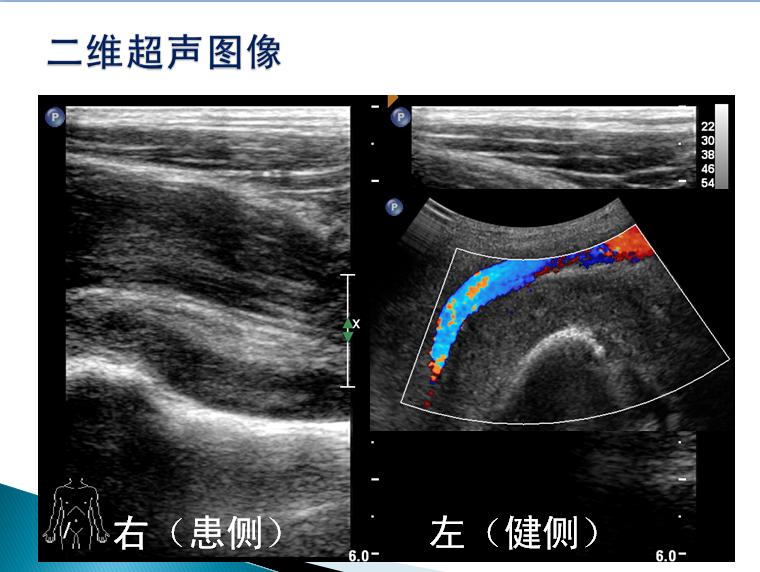

第三届中国超声造影大会病例大赛北医三院超声科获奖病例展示(三)